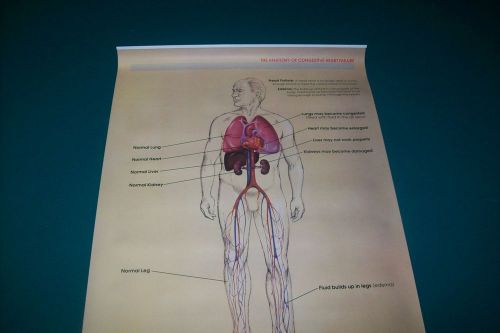

MEDICAL - Education Charts - Five: Muscle-Heart-Eye Disorder-Asthma- Male Repro

NEW POSTER Anatomy of HEART FAILURE Professional Wall Chart ROCHE LABORATORIES